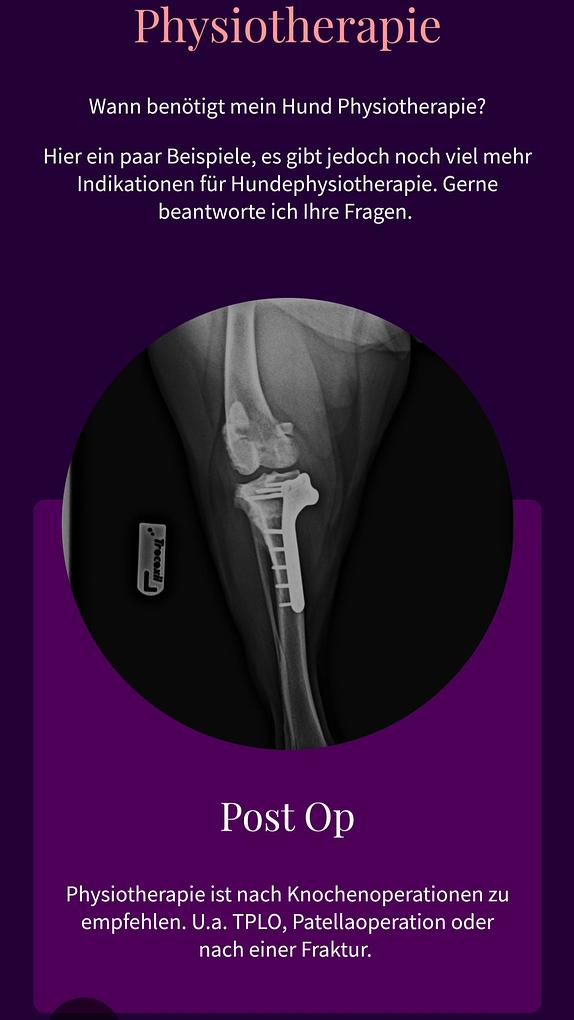

Tierphysiotherapie

Viele kennen und nutzen Physiotherapie als Mensch. Auch der 4 Beiner hat genau so einen Nutzen davon wie wir.

Im Alter als Entlastung, nach Operationen als Reha oder einfach, weil es ihnen gut tut....